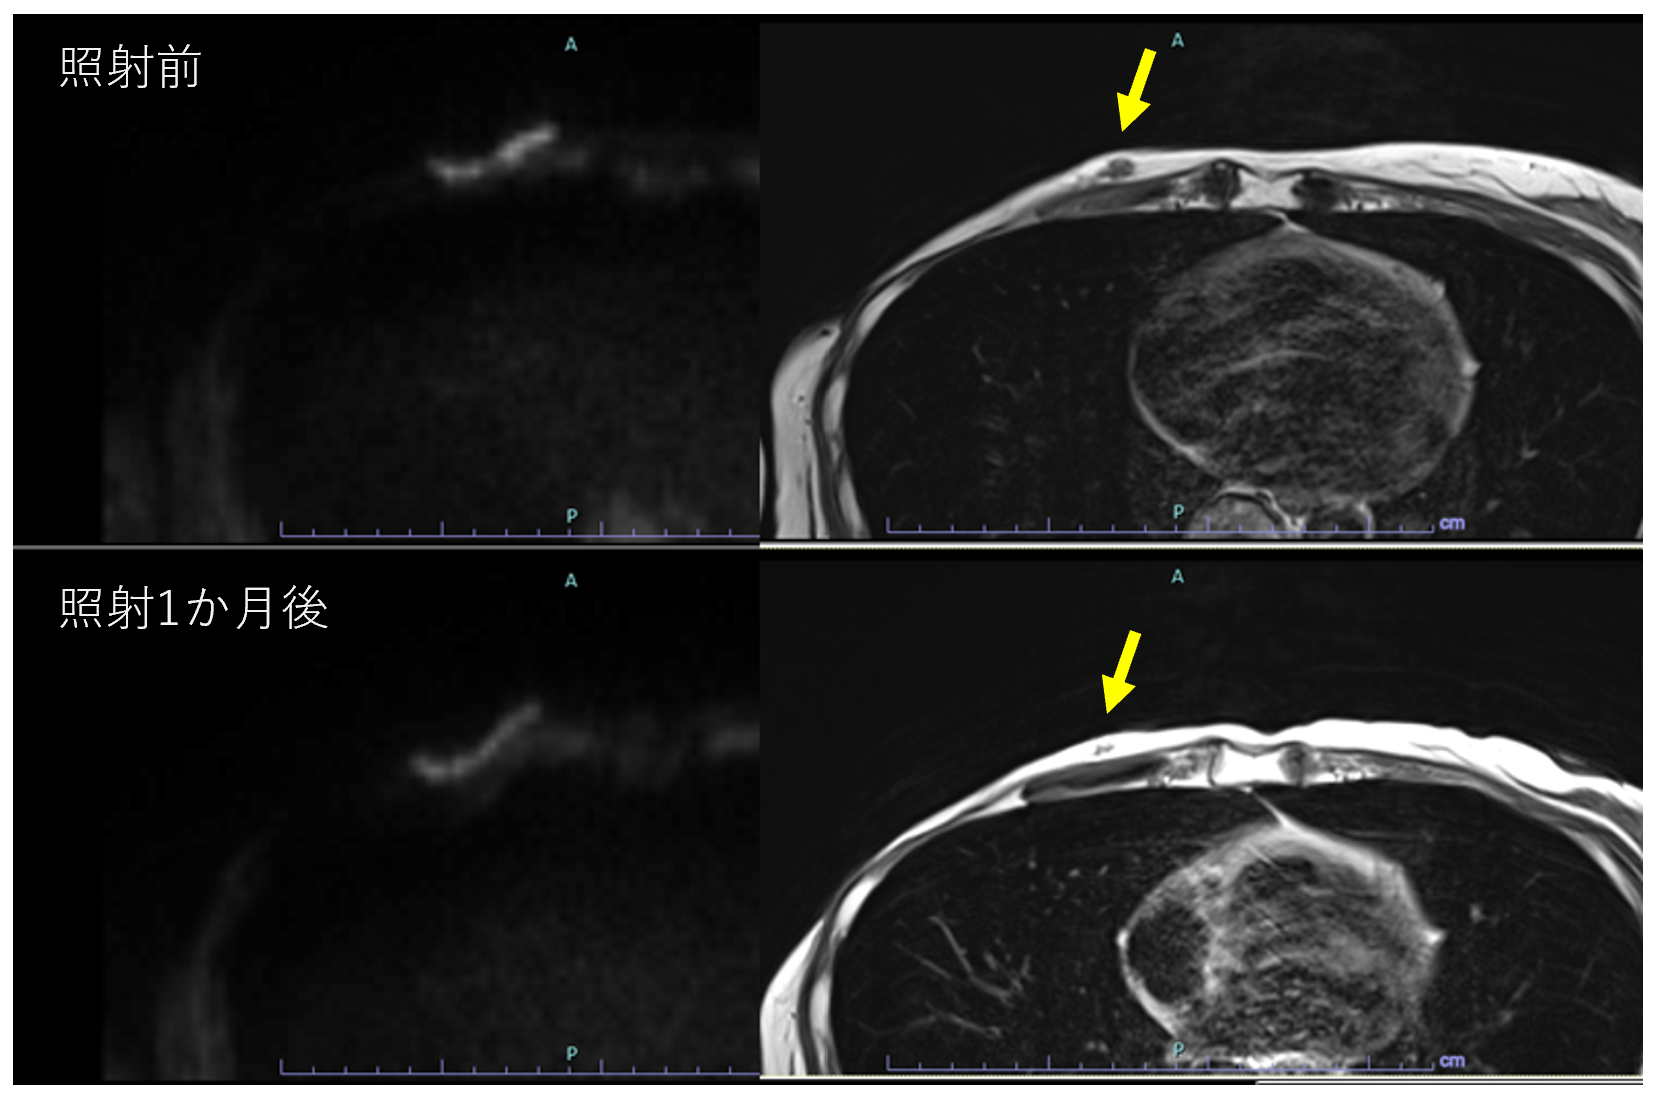

生まれのブランドで I19-175 2017年第10号10月号 臨床放射線 臨床医学